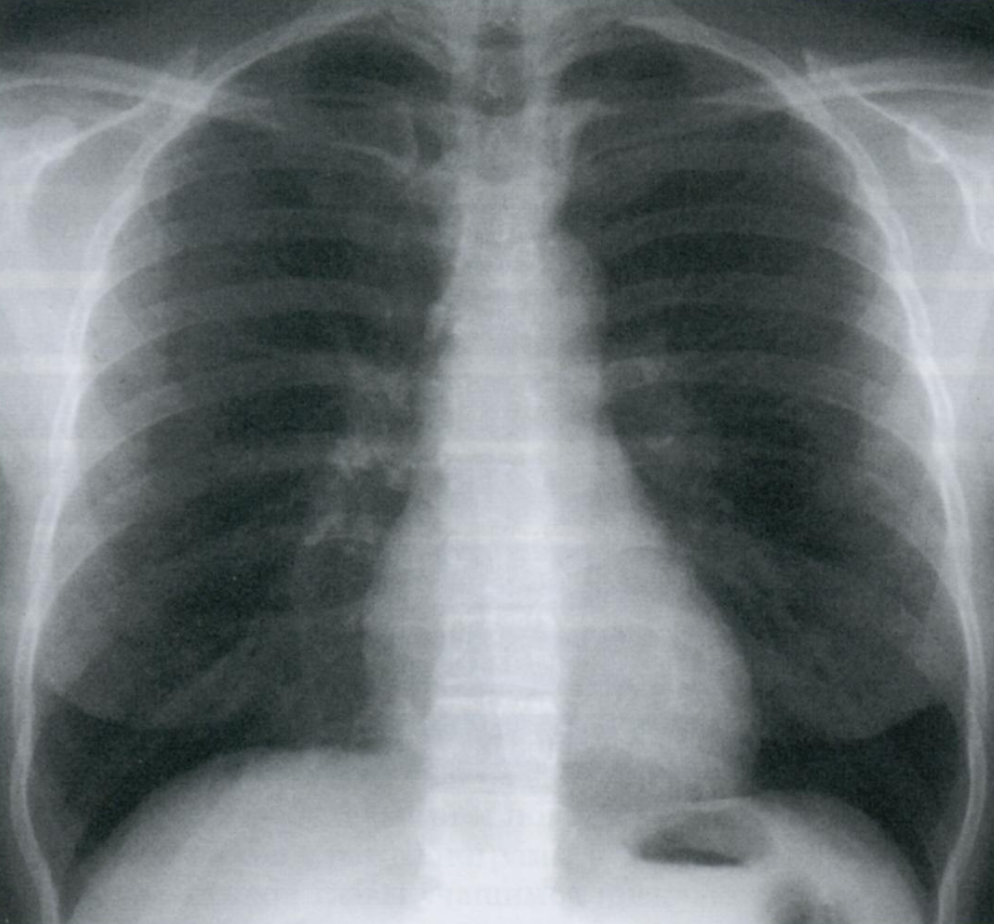

Q

Как расположены ребра на Rx грудной клетки?

Как выглядят верхушки легких на снимке?

Обратите внимание на верхушки легких. Что Вы ещё видите на снимке?

Обычно Rx выполняются при глубоком вдохе, когда в легком находится максимально возможное количество воздуха, и потому оно имеет наименьшую плотность. При корректно выполненом снимке на вдохе должны считаться 10 ребер по задней поверхности (или шесть по передней).

A

Задние сегменты ребер расположены горизонтально, передние проходят косо кпереди и книзу.

Верхушки легких, которые прикрыты первым ребром, могут выглядеть как участки сверхпрозрачности. Это обман зрения от перепада контрастности между ребром и верхушкой легкого.

Не перепутайте с буллой/пневмотораксом.

Rx грудной клетки на вдохе с признаками левостороннего пневмоторакса.

Normalmente las radiografías se toman en inspiración profunda, de manera que el pulmón tiene la mayor cantidad de aire posible y por tanto la menor densidad. En una placa correctamente inspirada deben poder contarse 10 costillas por su parte posterior (o seis por la anterior).